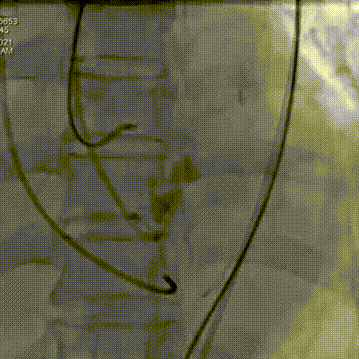

瓣膜完全释放后22mm球囊后扩

释放后造影

超声影像

血流动力学改善,瓣膜形态良好,少量瓣周漏